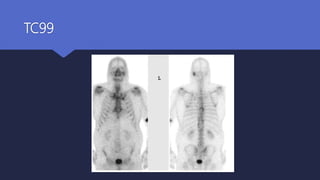

 TC 99 bone scan ------ Bone involvement

 Gallium 67 ------------- Monitoring

 Indium In 111-labeled leukocyte scans

Diagnosis Radiological investigations Radioisotope scans TC 99 bone scan ------ Bone involvement  Gallium 67 ------------- Monitoring  Indium In 111-labeled leukocyte scans

• #22 Fig. 2. Anterior and posterior views of technetium Tc 99m MDP bone scan of patient from Fig. 1showing increased uptake in the left mastoid.